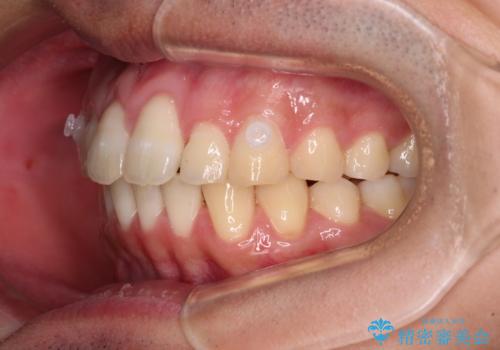

捻れて飛び出した前歯 インビザラインで整った前歯に

- 上下前歯のデコボコと、それに伴う出っ歯を気にして来院された患者様です。

インビザラインによる上下歯列の側方拡大と後方移動、IPR(歯と歯の間を削る)にるスペースの獲得により歯列を整えることとしました。

歯と歯の間を削ることでうまくスペースコントロールでき、また、毎日22時間以上しっかりとマウスピースを装着していただいたので、スムーズに治療が進みました。